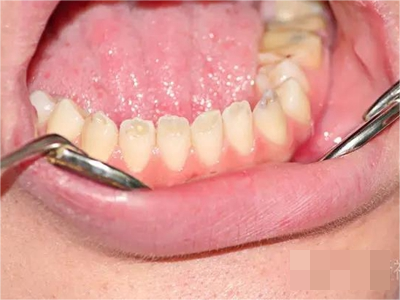

牙釉质发育不全牙齿褐色有一个小凹坑图

牙釉质发育不全累及单颗牙齿时,患者日常无明显的不适感觉,只是在照镜子时发现牙齿表面出现深褐色的沉积斑块,像是被咖啡等染色一样,但是无法刷掉,触摸时有小坑的感觉。